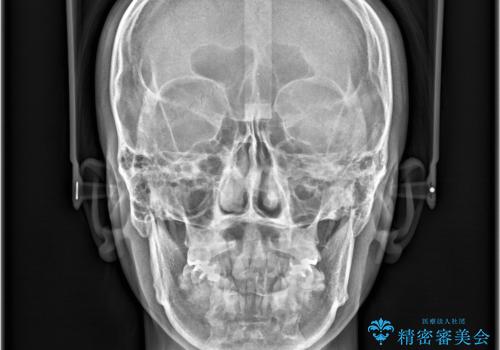

- 「歯のデコボコと前歯が引っ込んでいるのを治したい」を主訴に来院された患者様です。

デコボコの量が多かったため上下左右4を抜歯してワイヤー矯正で治療を行いました。

顔貌に対して歯の正中も合いました。